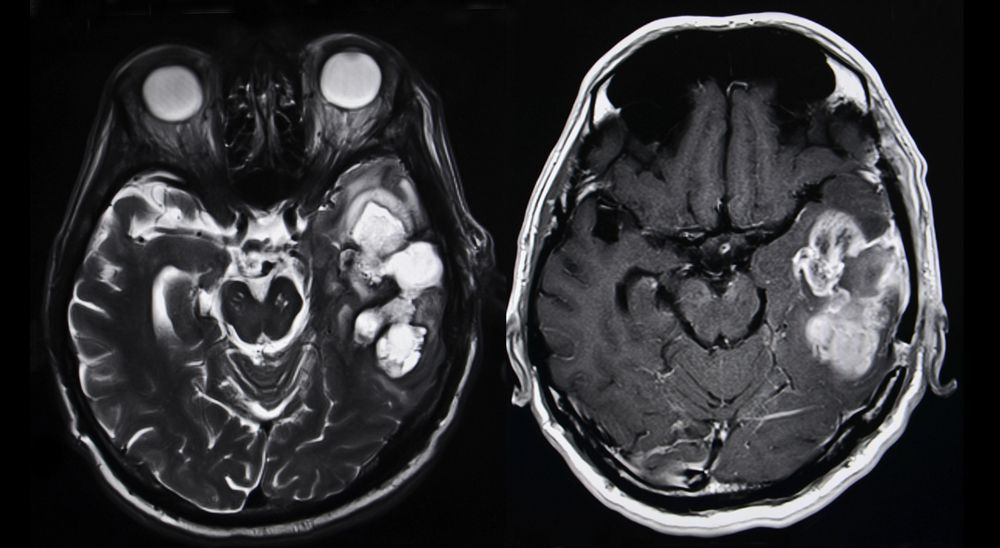

MGMT Methylation a Survival Biomarker in High-Risk Low-Grade Gliomas?

These are the first data to highlight the prognostic value of MGMT methylation beyond the IDH1/2 mutation status test currently used to help predict glioma patient survival outcomes.